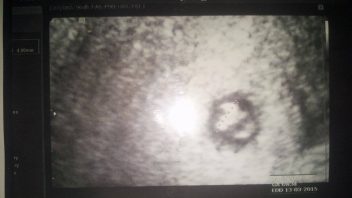

Ms se měla dostavit kolem 4.7.2014, testy vyšly pozitivně dne 8.7.2014 jsem navštivila svého ženského lékař,e zatím na utz v ten den nic nebylo pořadně vidět jen sliznice 13mm.

Na mou žádost mi odebral krev která prokázala ze hladina HCG je 385 čili 4tt.